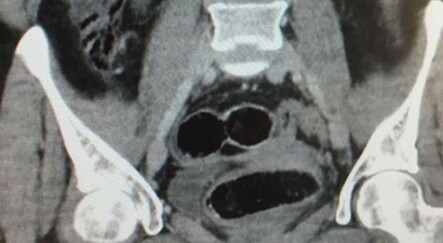

Ultrason ve röntgen filmi çekilen hastanın midesinde çok sayıda parça olduğu belirlendi. Bunun üzerine genel cerrahi Servisinde ameliyata alınan Z.D'nin midesinde, 1 liralık 83 madeni para, pil, mıknatıs, çivi, cam parçaları, taş ve vida gibi 233 malzeme çıkarıldı.

Genel Cerrahi Uzmanı Doktor Serhat Binici, yaptığı açıklamada, hastanın midesinde değişik çaplarda metal ve taş parçalarının olduğunu tespit ettikten sonra endoskopi yaptıklarını söyledi.

Midedeki parçaları görünce açık ameliyat yapmaya karar verdiklerini anlatan Binici, şu bilgileri verdi:

"Ameliyat esnasında çivilerden bir iki tanesinin mide duvarını geçtiğini gördük. Kalın bağırsakta değişik ebatlarda iki metal parça ve iki taş olduğunu izledik. Midesini açtığımızda pil, mıknatıs, çivi, metal para, cam parçası, vidalar olduğunu gördük. Midesini tamamen temizledik. Erişkin yaşlarda gördüğümüz bir durum değil, daha çok çocukluk çağında ve bilinçsizce yutulan yabancı cisimler oluyor. Erişkin yaş grubunda genelde psikiyatri hastaları, mahkumlar veya istismar olaylarında görülebiliyor."